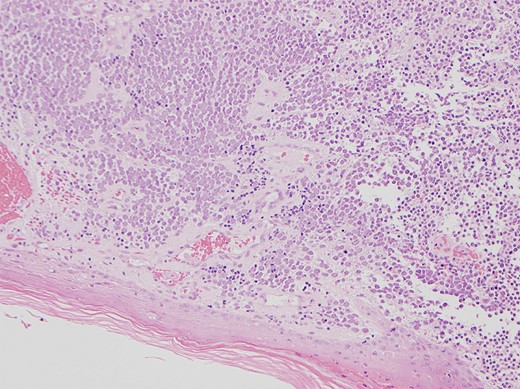

Physical examination revealed a 12 cm × 10 cm fungating soft tissue mass with no evidence of axillary or cervical lymphadenopathy. Following urgent magnetic resonance imaging of the lesion (Fig. 3), biopsies were obtained under local anaesthesia. Histology result identified an ulcerated and invasive tumour involving the dermis (Fig. 4). It was composed of sheets of monotonous atypical round cells with hyperchromatic nuclei. The tumour cells were positive for chromogranin, CD56 and CK20 and negative for S-100, TTF-1, LCA and Melan-A. These confirmed the diagnosis of MCC and the patient was thus treated with wide-local excision and radiotherapy. Further review at 6 months confirms the patient has had a good postoperative course and is free of local recurrence and distal metastases.

Shows the histology image of the biopsy sample with monotonous atypical round cells and hyperchromatic nuclei.